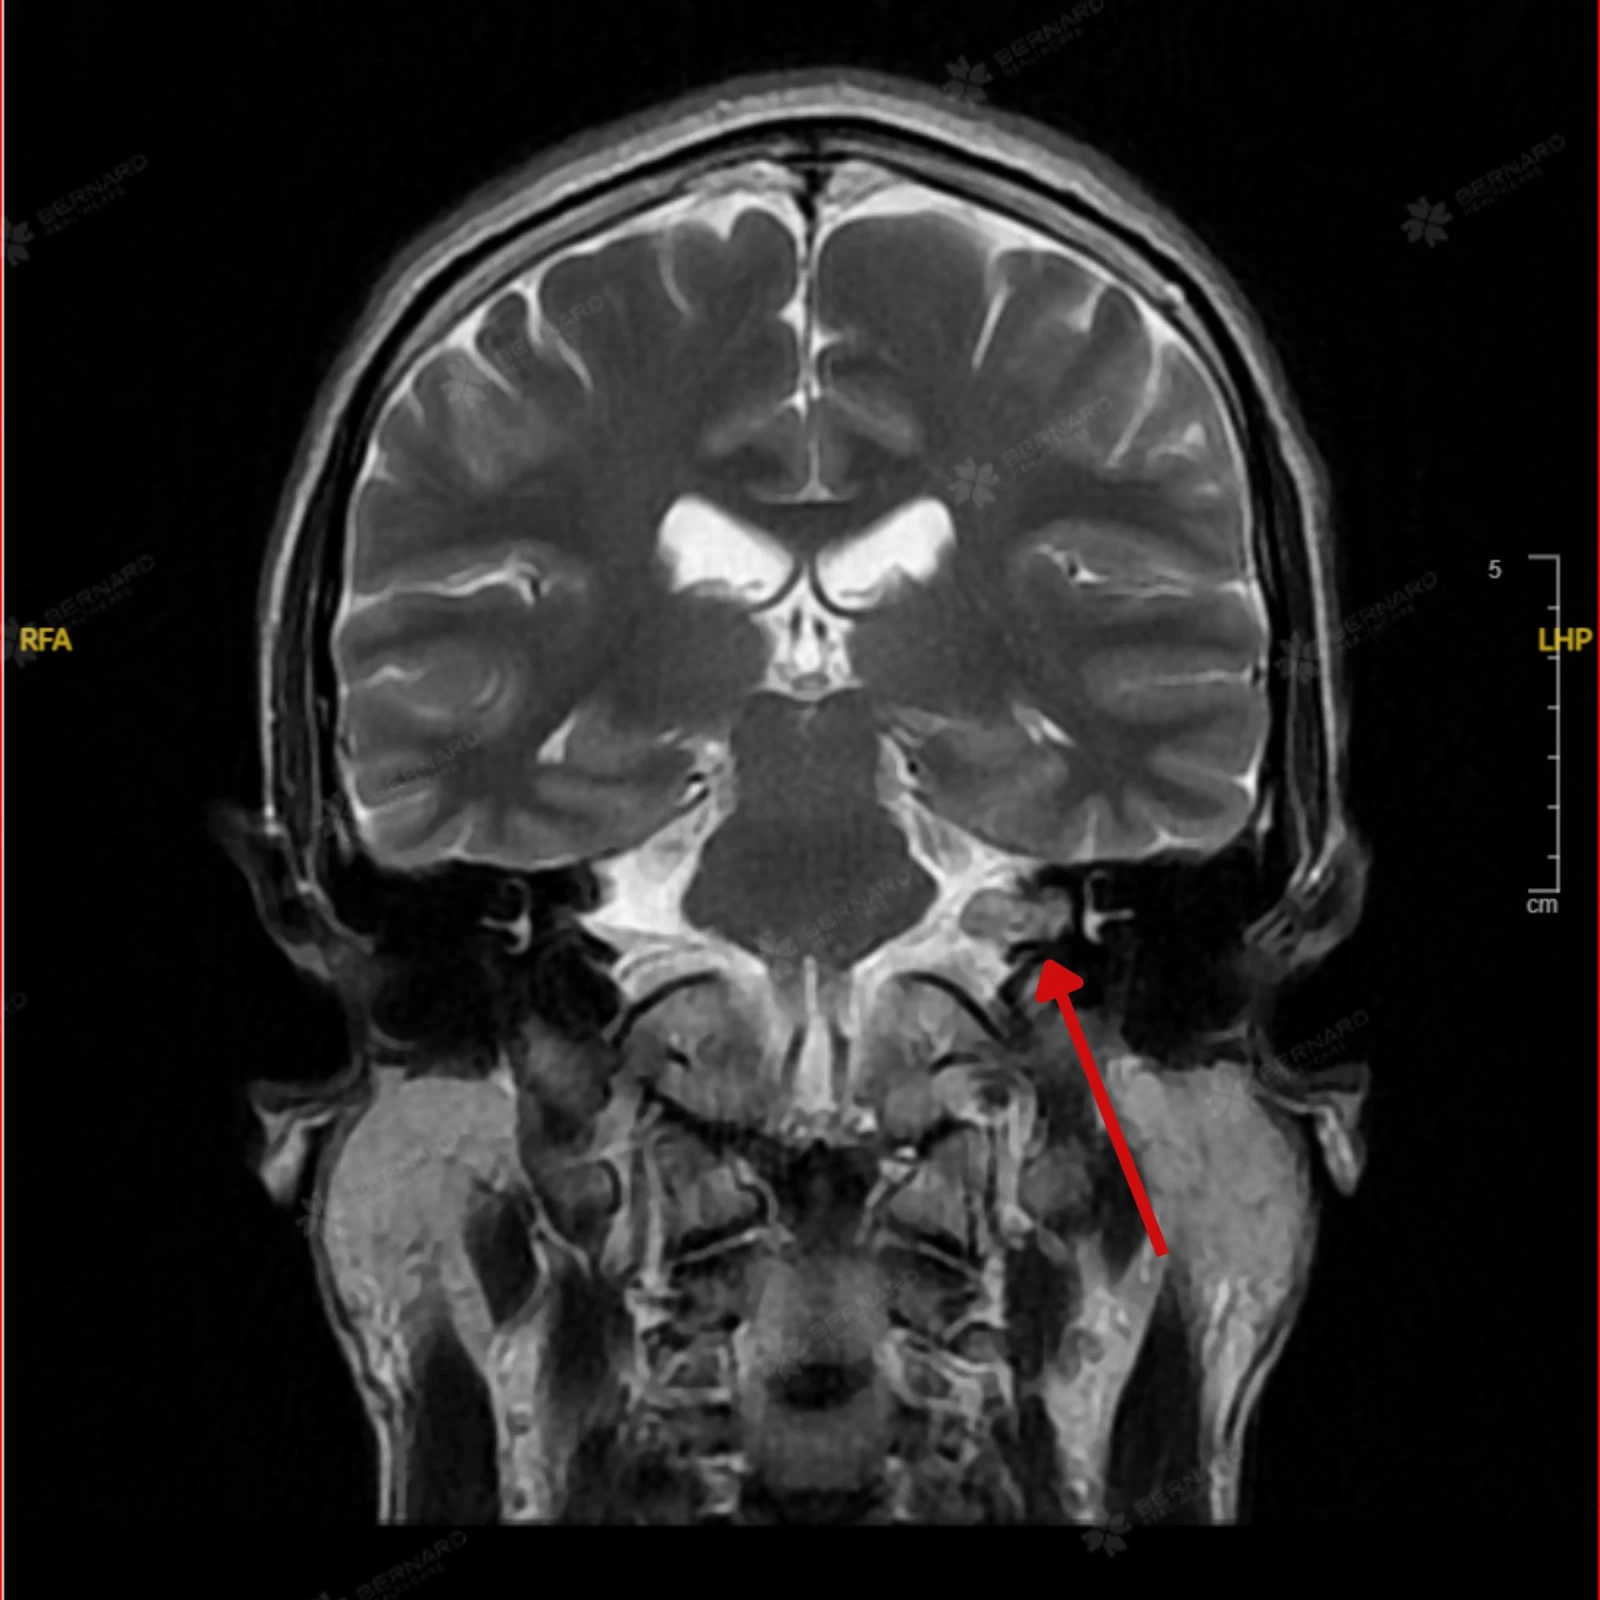

Kết quả MRI não ghi nhận: Tổn thương choán chỗ ngoài trục tại vùng góc cầu tiểu não trái, lan vào ống tai trong trái, kích thước khối u khoảng 10 x 12 x 16 mm. Hình ảnh tổn thương gợi ý u góc cầu tiểu não trái lan vào ống tai trong, nghĩ nhiều đến schwannoma (u bao dây thần kinh).